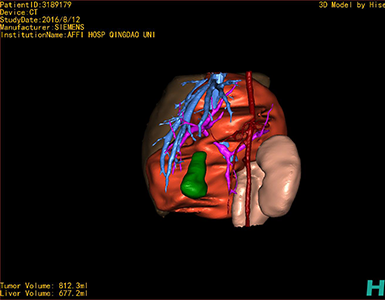

将0.625mm双源薄层CT资料的静脉期和动脉期Dicom格式文件导入海信CAS系统。

通过调节窗宽窗位调整CT序号,对肿瘤,肝实质,胆囊,下腔静脉,肿瘤,肝动脉、门静脉及肝静脉等进行三维重建;系统自动计算肿瘤体积和肝脏体积。

模拟手术操作,自动计算切除肿瘤体积。肝脏体积为660.9ml,肿瘤体积为812.3ml,肿瘤体积为肝脏体积的122.9%,通过比对3-4岁正常肝脏体积为522.63±121.24 ml,肿瘤所占比例较大,且包裹右侧肾脏、及腹腔大血管,手术无法完整切除肿物,不建议给予手术治疗。